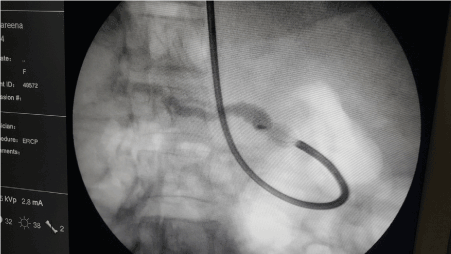

Figure 2. Impacted wire basket with a stone.

Extraction with a wire basket (Olympus-Tetra Catch V-FG-V432P) was attempted. Few smaller calculi were removed, however, while attempting to retrieve a larger stone, the wire basket got impacted within the PD, just distal to the ampulla. Attempts at releasing the basket failed. Then the wire of the basket was divided at the handle and the scope was removed. The wire of the basket was attached to the Mechanical lithotriptor (Olympus BML-11OA-1). While attempting to crush the wire of the baskets broke from the proximal end.